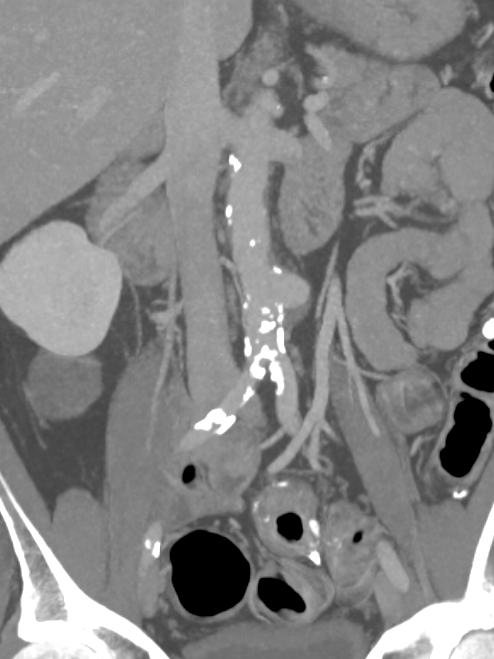

He underwent a CT scan which showed a 5 cm dilatation of his large artery in the abdomen called aorta (saccular infrarenal aortic aneurysm).